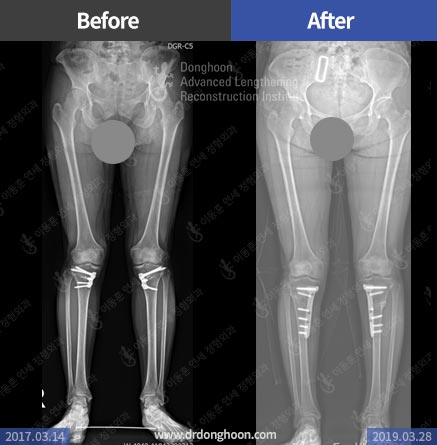

절골술 후 재수술이란

관절염의 치료를 위해 절골술을 할 경우 많은 경우에 의도적으로 약간의 과교정 (over-correction )을 하게 되는데 이것은 이미 손상된 부분에 체중이 걸리지 않고 가능한 건강한 부위에 체중이 많이 가도록 하기 위한 것입니다.

하지만 이런 과교정의 정도를 잘 조절하지 못하여 ‘지나친 과교정’을 하게 되면 심각한 결과를 가지고 올 수 있는데, 실제 관절염 절골술이 많이 시행되면서 이런 문제로 우리를 찾아오는 분들이 많아지고 있습니다. 이 경우 재수술을 통하여 올바른 다리 정렬을 만들어야 합니다.